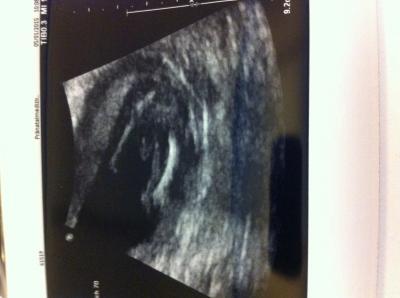

Das ist einer von meinen beiden zwillis Jungs ! Gestern erfahren bei 14+4 Wie sahen Euere aus ?!

Bild zu Habt ihr Jungs outing Bilder? - Schwanger - wer noch? Rund um die Schwangerschaft